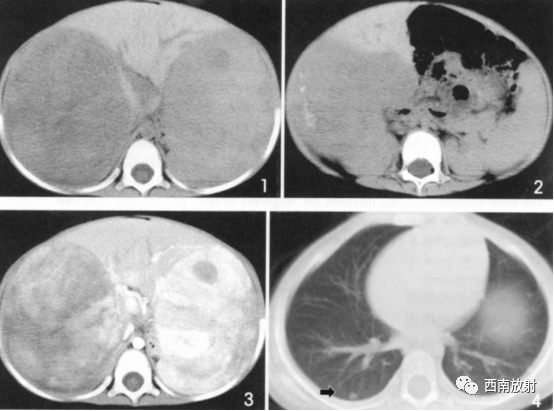

▲病例2:肝母细胞瘤。图1:CT平扫肝左右叶肿块,呈低密度,内部密度不均。图2肝内可见钙化灶。图3增强扫描肝内病灶不均匀明显强化,片状或结节状强化,见假包膜结构,图4可见肝内转移灶。